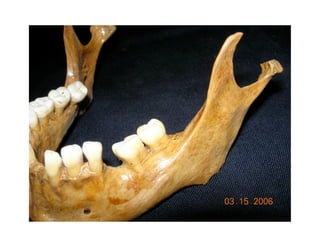

Este documento describe los principios de construcción de la arquitectura craneofacial, incluyendo el metamerismo, la simetría y la paquimería. Explica la organización peri-cavitaria del cráneo a través de columnas y vigas, y analiza las diferentes fascias profundas del cuello. También destaca la importancia de conocer la irrigación ósea con orientación quirúrgica, mencionando los principales aportes vasculares y suplementarios así como el origen, trayecto y retorno venoso de la carót